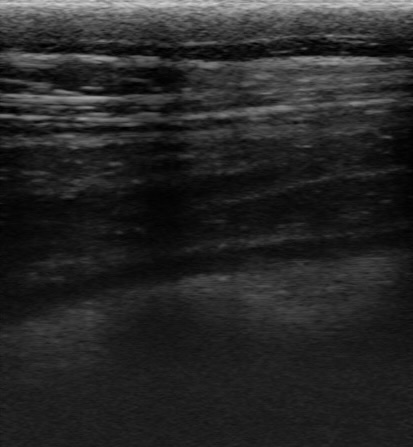

比較のため、隣にいた健常牛でも同じ部位で撮影してみます。

健常牛

こうしてみると、先に見た牛に異常があることが一目瞭然ですね!